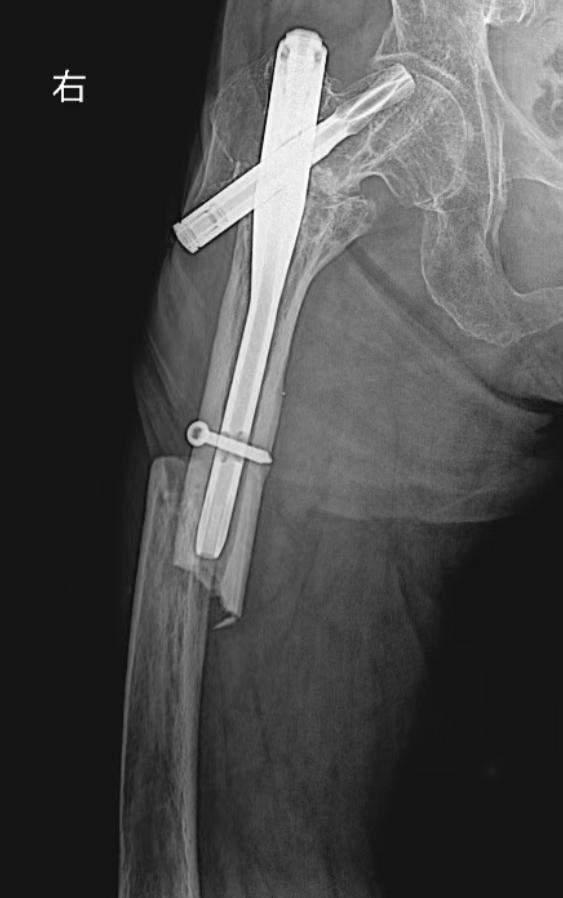

手术由骨三科团队精心实施,以微创为核心,在精准操作下巧妙处理了新旧伤情,极大降低了手术创伤。术后,科室医护团队全程精细管理,结合系统化、个性化的康复方案,循序渐进指导功能锻炼。在医疗技术与人文关怀的双重护航下,化奶奶的骨折顺利愈合,肢体功能得到显著恢复,最终成功放下了依赖十二年的拐杖,实现了独立行走的夙愿。

术后